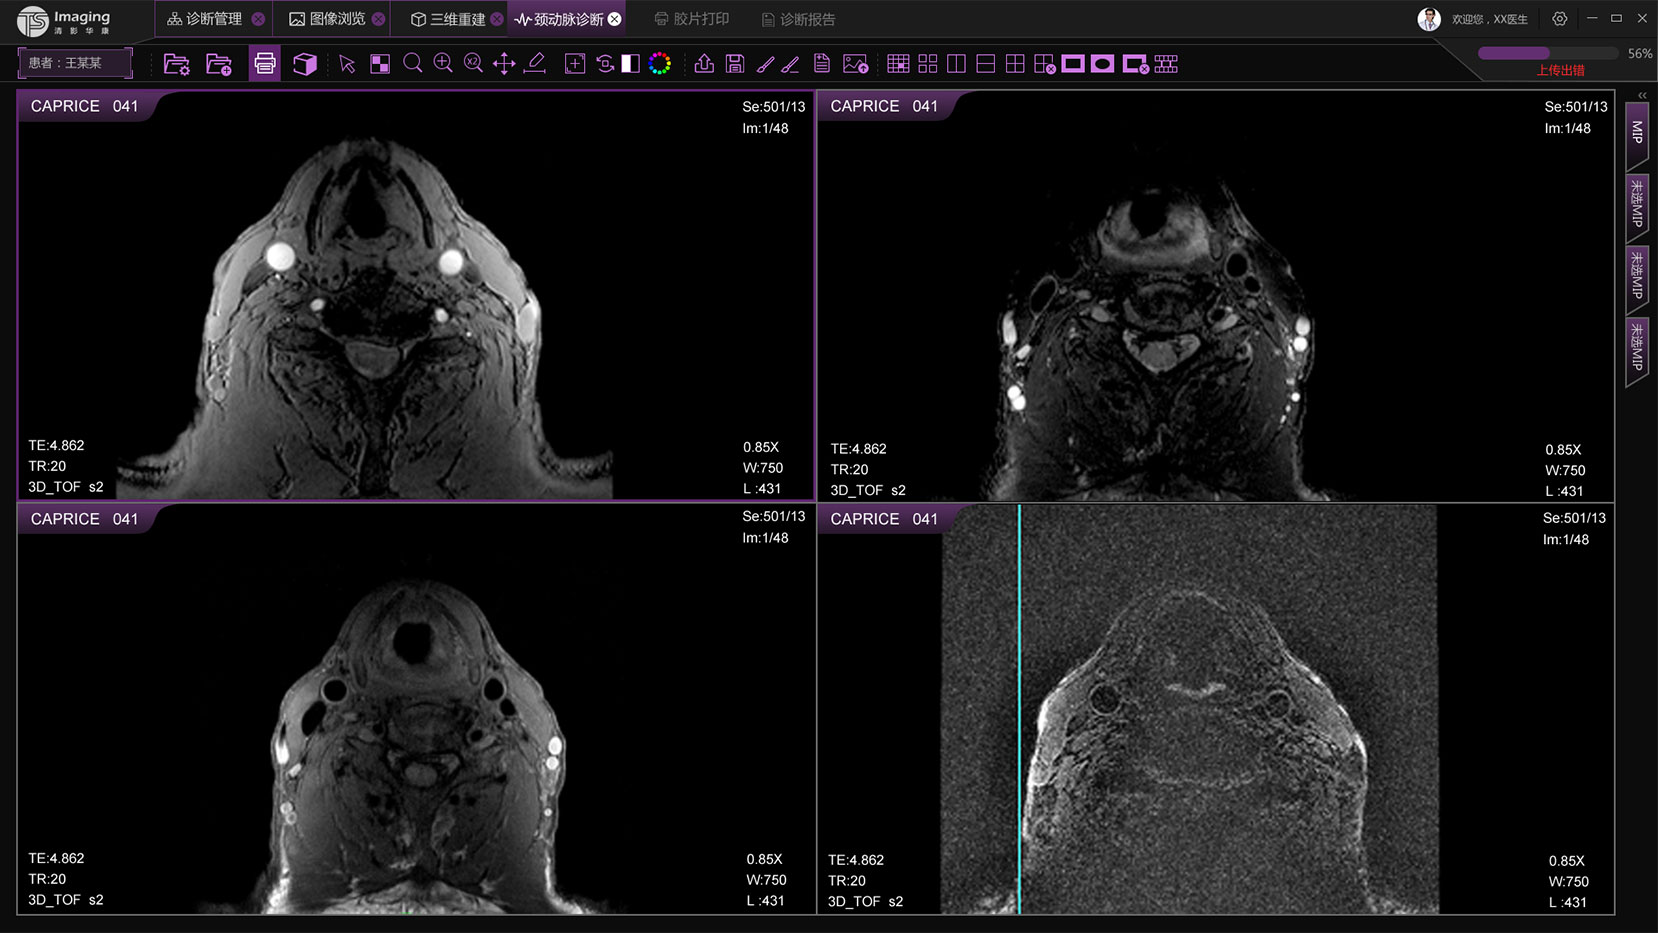

頸動(dòng)脈診斷頁面

頸動(dòng)脈診斷頁面整體布局和三維重建比較相似,最大的區(qū)別是右側(cè)的操作區(qū)域,血管分析都為按鍵操作,通過間隔的大小分成三部分。單層切片除了按鍵還有下拉菜單的操作。